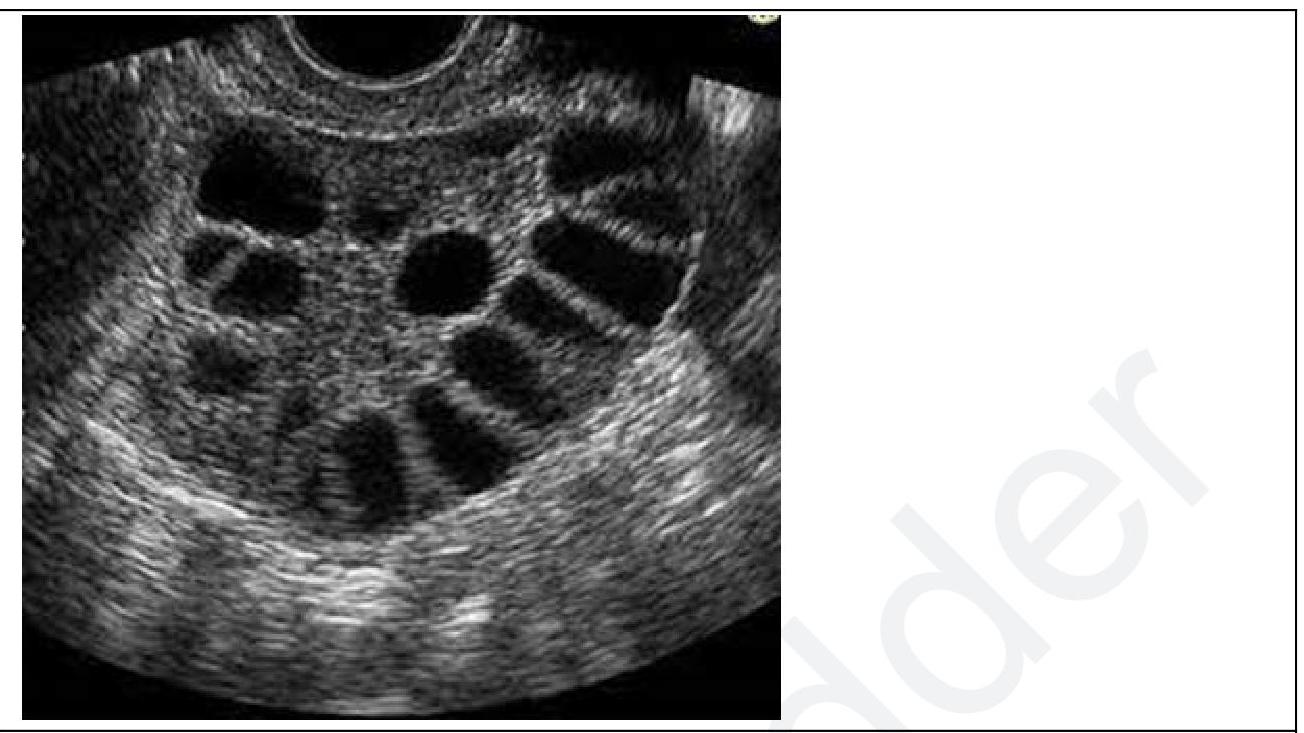

A lady on treatment for infertility developed ascites, abdominal pain, and dyspnea. An ultrasound (USG) of the patient was done. What will be the diagnosis?

Explanation: ***Ovarian Hyperstimulation Syndrome (OHSS)*** - The clinical presentation of infertility treatment followed by **ascites, abdominal pain, and dyspnea** is highly suggestive of OHSS. The ultrasound image shows **enlarged ovaries with multiple follicular cysts**, which is characteristic of severe OHSS. - OHSS is a potentially serious complication of **ovarian stimulation** during infertility treatment, where excessive ovarian response leads to systemic changes from increased vascular permeability. *Theca lutein cysts* - These cysts typically develop due to **excessive stimulation by hCG**, often seen with gestational trophoblastic disease or multiple pregnancies. - While they can be large and multiple, they are not typically associated with the rapid onset of severe systemic symptoms like **ascites and dyspnea** in the context of infertility treatment directly. *Mucinous cystadenoma* - This is a type of **benign ovarian tumor** that can grow very large and cause abdominal distension, but it is not typically associated with infertility treatment or the acute systemic symptoms of ascites and dyspnea as seen here. - Imaging would typically show a **multilocular cyst with internal septations**, not the numerous small follicular cysts seen in the image. *Polycystic Ovary Syndrome (PCOS)* - PCOS is a common cause of infertility, characterized by **anovulation, hyperandrogenism, and polycystic ovaries** on ultrasound (multiple small follicles in a string-of-pearls pattern). - While the ultrasound shares some similarities with multiple follicles, PCOS does not cause the acute symptoms of **ascites, abdominal pain, and dyspnea** that are directly linked to the rapid onset of severe OHSS.